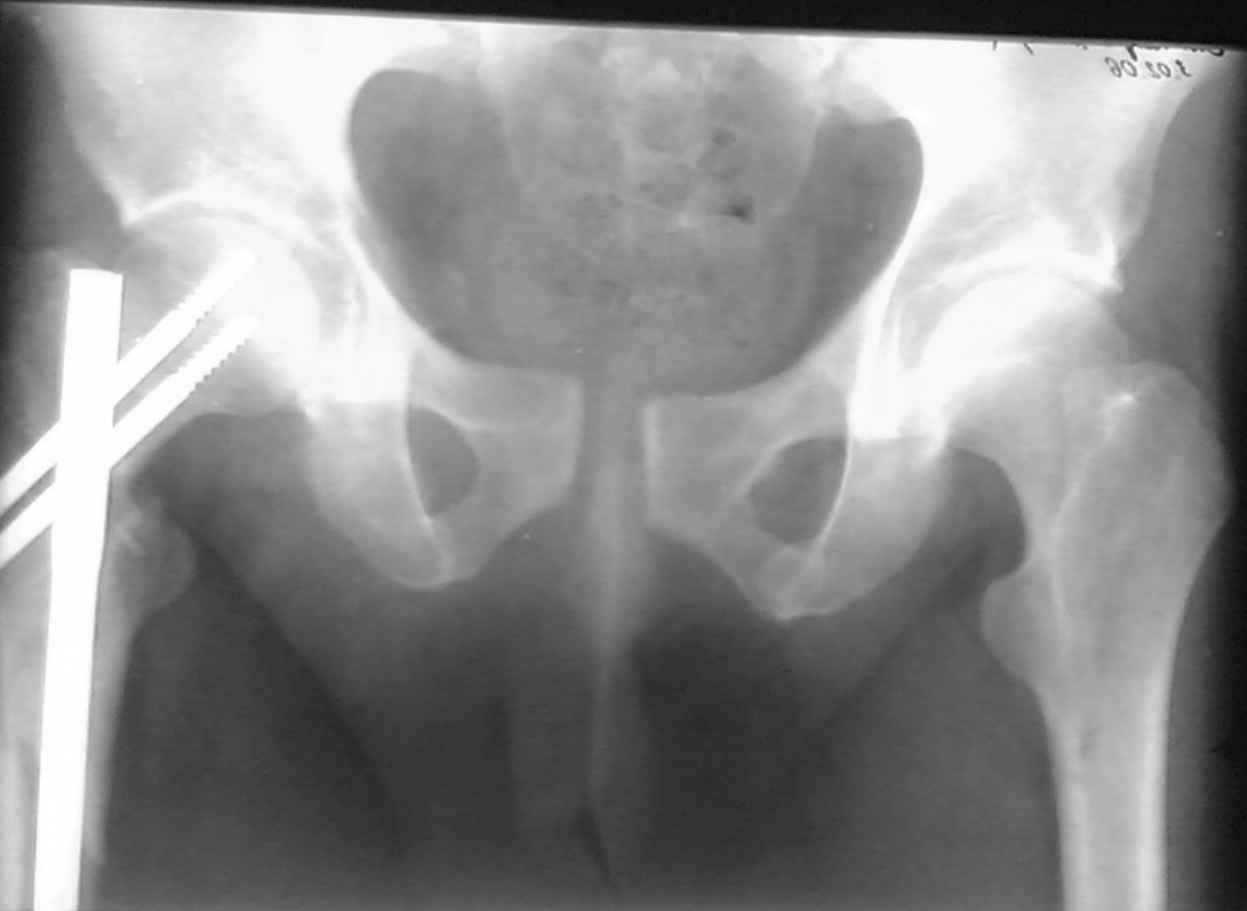

извините за опоздание , вот фотографии

<На R-мме таза ( в прямой проекции, вход и выход из таза) определяется изолированный разрыв лонного сочленения с диастазом 4см,расширение щели правого КПС(вертикальной нестабильности нет, >

Разрыв лонного сочленения с диастазом более 2,5 см говорит о полном разрыве крестцово-подвздошного сочленения (вертикальная нестабильность) или двустороннем характере повреждения (к/п с обеих сторон)

В представленном случае повреждение несомненно ротационное и реальный диастаз как раз около пограничных 2,5 см, репозиция идеальная, достигнута в первые дни после травмы. Я бы ограничился 3 мес фиксации в аппарате с ограничением нагрузки первый месяц, и функциональными снимками в 6 -8 недель.